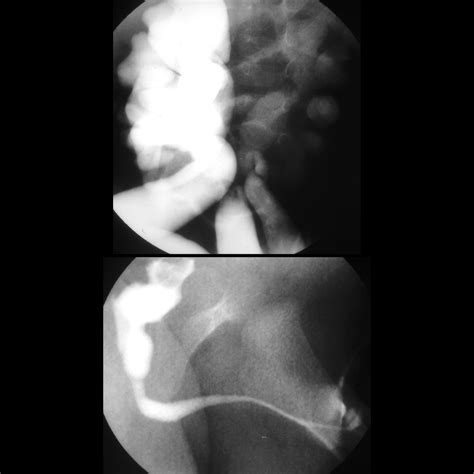

• Voiding cystourethrogram (VCUG): A special X-ray that shows the flow of urine from the bladder through the urethra.